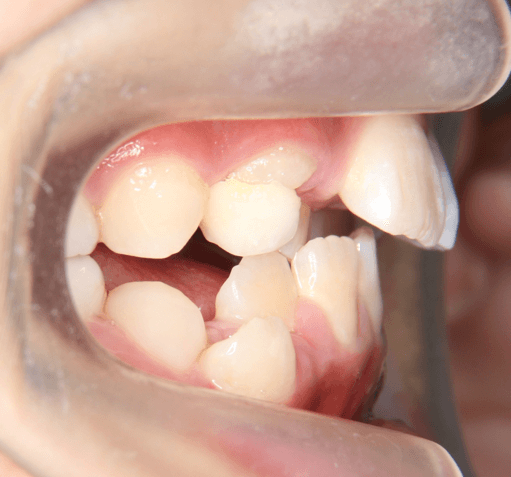

早期矯正治療 叢生症例② 翼状捻転

主訴 | 歯並びの乱れを気にされて来院された患者様です。将来的なスペース不足と歯のねじれ(翼状捻転)が懸念されました。 |

---|---|

診断結果 | 8歳9か月の女児。 歯列全体に叢生(乱れ)が認められました。翼状捻転による咬合不調も確認されています。 |

治療内容 |

|

治療後の経過 | 動的治療は2年10か月で終了後も3〜4か月ごとに定期検診を実施し、上下顎骨の成長発育が落ち着いてから本格矯正治療を行います。 |

治療期間 | 動的治療期間:2年10か月 通院回数:19回 |

治療費用 | 430,000円(税別) |